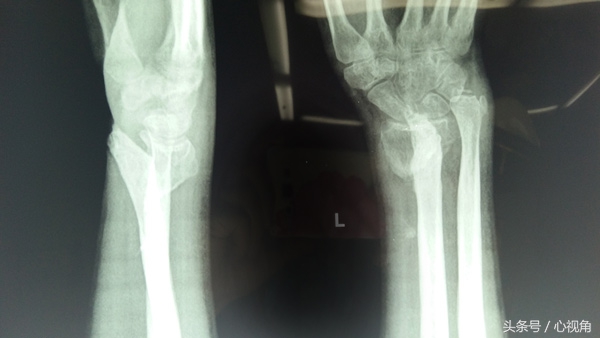

术前,陈旧性骨折至左腕部出现畸形

X光片

对此,王师傅当机立断,决定赴昆求医。后来,在一亲戚的介绍下,父子二人慕名来到昆明骨科医院。经完善检查后,志勇被诊断为左桡骨远端陈旧性骨折并正中神经、尺神经损伤;左下尺桡关节分离,左手缺血性挛缩。针对具体病情,医生介绍,患者右腕部骨骼畸形愈合,腕关节及各掌指关节活动受限,左手感觉麻木。